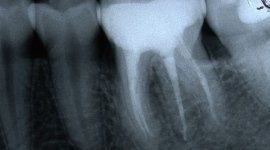

L’enorme diffusione ancora oggi riscontrabile della carie dentaria, unita a traumi, difetti di mineralizzazione o ipoplasie dello smalto determinano la necessità di dover ricorrere ad un restauro dei tessuti dentari lesionati. Il continuo miglioramento dei materiali e di conseguenza delle tecniche hanno altresì ampliato il raggio di azione della cosiddetta conservativa che con il ricorso al trattamento endodontico in caso di lesioni particolarmente gravi, occupa circa i due terzi dell’attività del dentista. In considerazione di questo fatto quindi, oltre all’evidenza che il trattamento restaurativo diretto è in genere il primo atto odontoiatrico che si effettua su una corona dentale lesionata, emerge la necessità che questa terapia sia ben eseguita ed in armonico rapporto con le strutture parodontali ed endodontiche.

Il trattamento endodontico

P3: Il trattamento endodontico si rende necessario quando la polpa del dente, comunemente chiamata dai Pazienti “nervo” è stata irrimediabilmente danneggiata da carie penetranti, fratture dentali, traumi o da cause imputabili a pratiche odontoiatriche scorrette. A volte la devitalizzazione del dente si rende necessaria, in corso di riabilitazioni protesiche complesse, per prevenire possibili problemi di ipersensibilità o per poter coinvolgere nel progetto terapeutico di recupero denti già di per se compromessi dal punto di vista parodontale. Presupposto per ottenere il successo in tale terapia è l’applicazione di un serio protocollo operativo che prevede tra l’altro l’uso di un telo di lattice, chiamato comunemente “diga”, che consenta la detersione e la pulizia dei canali del dente in un ambiente sterile e il controllo delle diverse fasi del trattamento attraverso delle radiografie endorali.